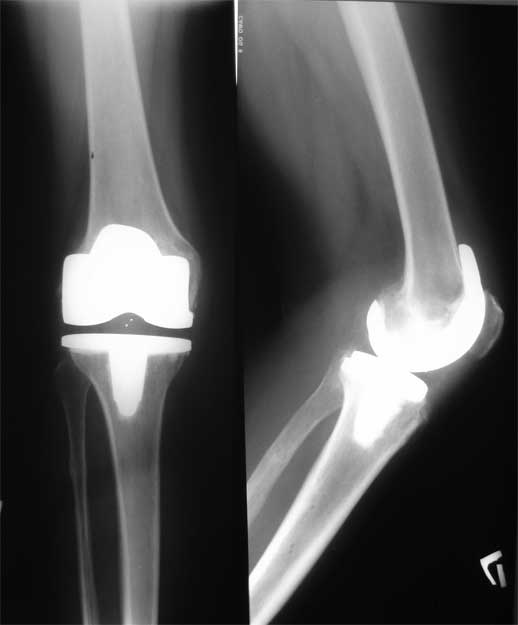

Уважаемые коллеги, пациентка 45 лет около 9 мес назад была прооперирована по поводу правостороннего коксартроза э/п LCS Complete RP.

послеоперационный период без особенностей, объем движений в 6 мес с/р - 110/0/0. Через 9 мес после операции возник напряженный гемартроз (без травмы, перегрузок), получено до 190 мл свежей крови, далее фиксация в ортезе, повторные пункции. через 2 нед выписана из стационара без признаков гемартроза. Через 2 нед аналогичная ситуация. Вопросы :причина? как лечить?

Был случай рецидивирующего гемартроза. Ангиохирурги, после ангиографии и УЗДГ сосудов, назвали это псевдоаневризмой и выполнили эндовазальную эмболизацию (кажется "стент")

Кликните для загрузки файла стент.jpg